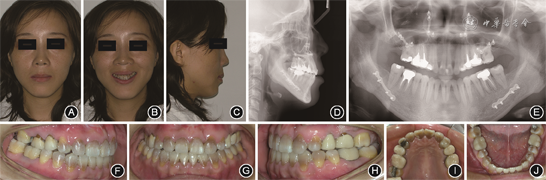

(1)颜面检查:正面观左右基本对称;侧面观为凹面型,鼻旁区凹陷,颏部前突。

(2)口内检查:恒牙列,12缺失,上下牙弓尖圆形,下前牙拥挤;上中线较面中线右偏3 mm,下中线与面中线基本对齐;双侧磨牙为近中关系;前牙覆

0 mm,反覆盖2 mm;全口牙颈部颜色发黄,口腔卫生良好。

(3)颞下颌关节检查:开口度正常,开口型正常,双侧颞下颌关节无张口弹响与杂音,无明显压痛。

(4)X线检查:头颅侧位X片及头影测量分析显示,患者为骨性Ⅲ类[ANB角(上牙槽座点、鼻根点与下牙槽座点构成的角)为-5.2°],高角型[FMA角(眼耳平面与下颌平面的交角)为40.6°],上颌骨发育不足,下颌骨发育过度,上切牙代偿性唇倾,下切牙代偿性舌倾。曲面体层X线片显示14、17、24、47冠内高密度影,15、16、22、25、26、36、46冠及根管内高密度影,余牙牙根未见明显异常;全口牙牙槽骨水平吸收;关节区未见明显异常(图1)。

成年患者治疗前面像、口内像和影像学资料 A:正面像;B:正面微笑像;C:侧面像;D:头颅侧位X线片;E:曲面体层X线片;F:右侧

像;G:正面

像;H:右侧

像;I:上颌

面像;J:下颌

面像